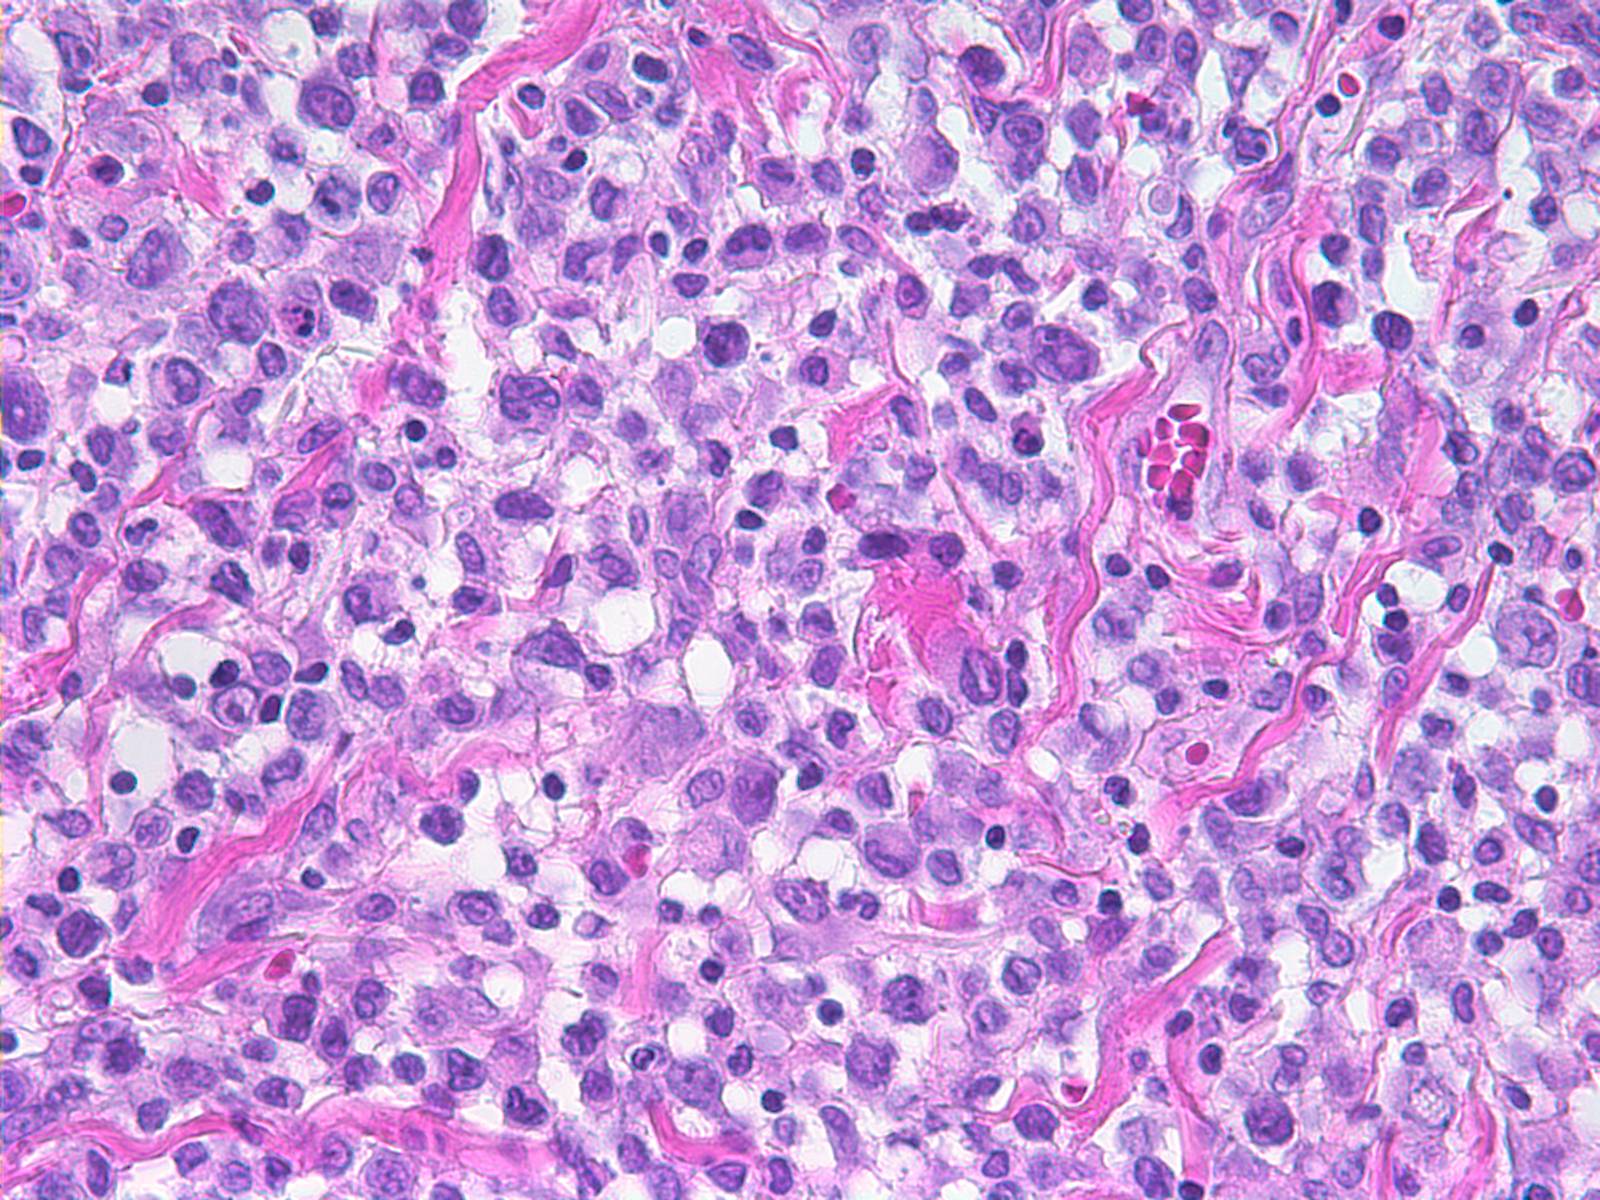

The Hematopathology service at UMass Memorial Medical Center provides skilled interpretation of specimens from the bone marrow, lymph node, spleen and extranodal sites. We have a special interest in histiocytic proliferative disorders, cutaneous lymphoproliferative disease and flow cytometric diagnosis.